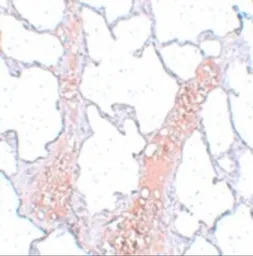

IHC-P analysis of rat lung tissue using GTX31981 REEP2 antibody.

Working concentration : 20 μg/ml